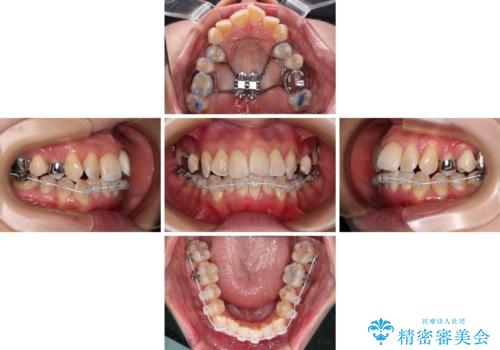

3. 終了時

3. 【モニター】急速拡大装置 狭い歯列を拡大してワイヤー装置で短期間治療の治療後